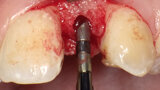

Aproximální rozšíření mezi kořeny zubů za účelem zavedení úzkého implantátu